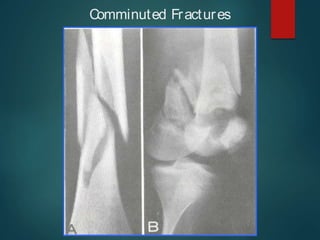

-Comminuted Fracture.

Comminuted Fractures

Complete Fractures